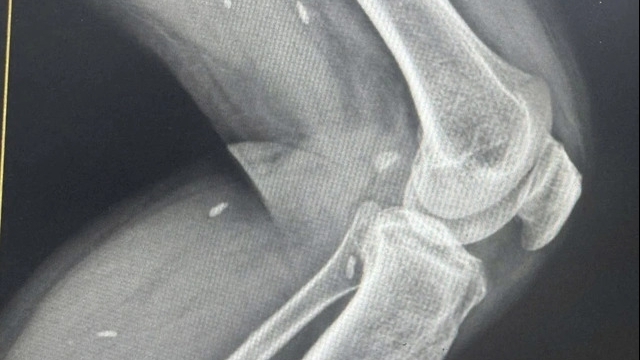

| Một vụ việc vi phạm an toàn thực phẩm. |